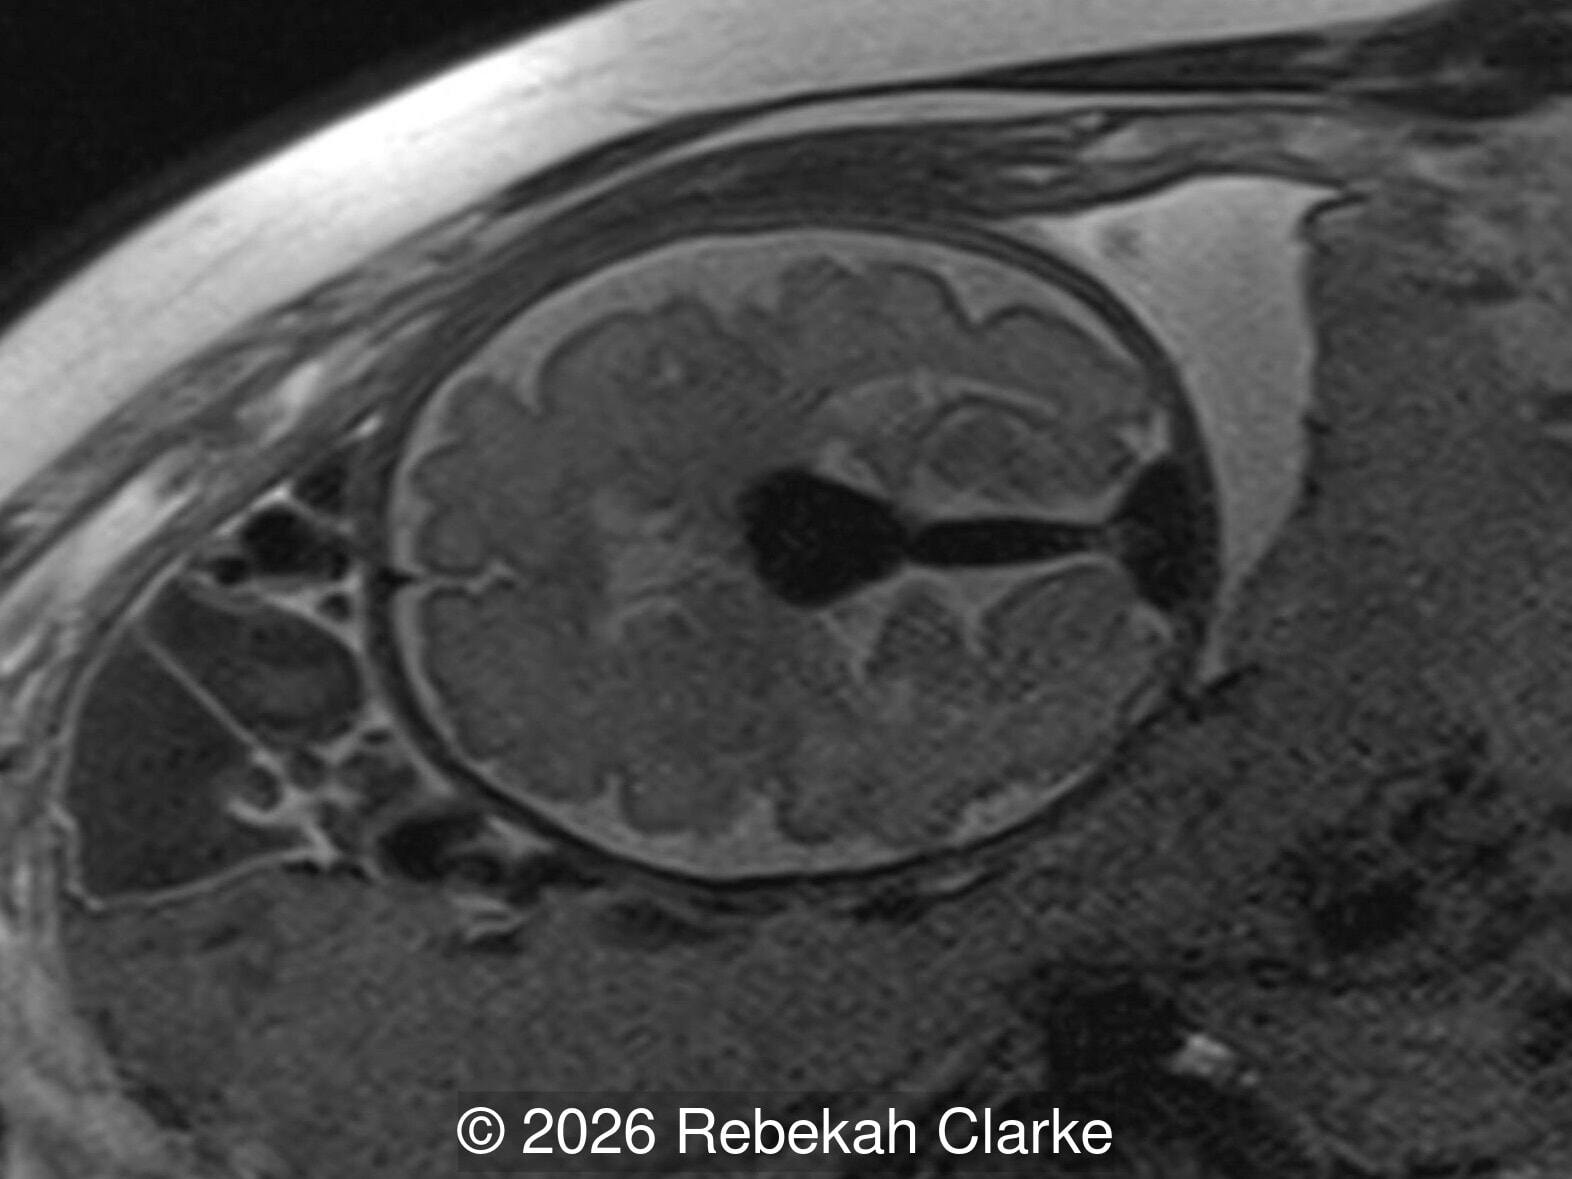

The diagnosis was confirmed by fetal magnetic resonance imaging (MRI). Our patient did not meet the criteria for in utero embolization. At 37 weeks she was delivered via cesarean section and underwent postnatal embolization.

Axial T2-weighted image through the fetal brain at the level of the cavum septum pellucidum, showing the prominent T2 hypointense flow void of the vein of Galen malformation.

Image 6 Axial T2-weighted image through the fetal brain at the level of the cavum septum pellucidum, showing the prominent T2 hypointense flow void of the vein of Galen malformation.